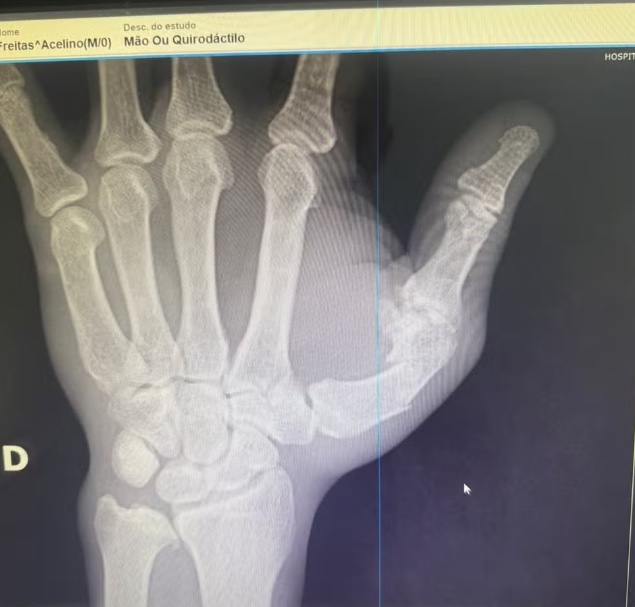

Exames de raio-X indicaram uma fratura diafisária do primeiro metacarpo, osso fundamental para a mobilidade do polegar. Segundo especialistas, o procedimento cirúrgico é necessário devido ao desvio do osso e visa reduzir o risco de sequelas funcionais, garantindo uma reabilitação mais rápida. A operação deve durar cerca de 2h30, e Popó permanece clinicamente estável, sem fraturas cranianas, apesar de ter apresentado um sangramento interno já controlado.